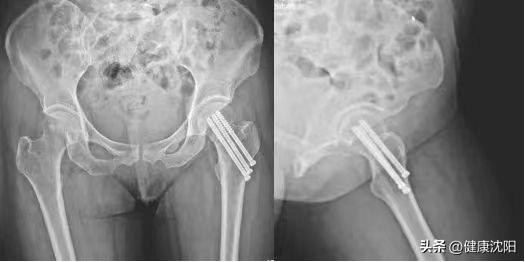

1.闭合复位空心钉内固定。它具有创伤较小、手术耗时短、对股骨头血供破坏较小、术后明显缓解疼痛等。

优点:微创且费用低的手术方法。

缺点:恢复期长,卧床,仍有股骨头坏死可能,若发生股骨头坏死则需行髋关节置换术。